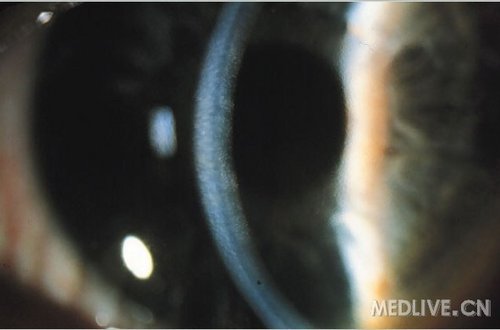

Bullous keratopathy(大泡性角膜病变)